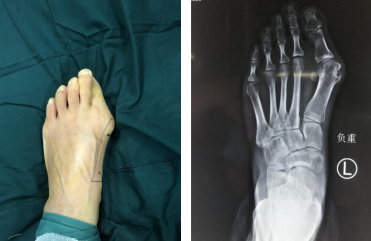

35岁的张女士10年前发现双足拇外翻畸形,前足增宽,未予重视。随时间增长,双足拇外翻畸形程度逐渐加重,拇囊突出,不能长时间负重行走及久站。近1年双足负重行走时足底疼痛明显,左侧症状较重,为进一步治疗,来我院就诊,门诊拟“双足后天性拇外翻畸形”收治入院。

术前

石荣剑副院长、曹广超主任、赵亮医生团队为患者行左足拇外翻矫形手术。术中于左足第一跖骨头端内侧做一长约5毫米微小切口,利用超声骨刀行跖骨远端外移截骨,远端向外侧推移、向跖侧下压,使用全螺纹空心螺钉固定。术后患者恢复良好。